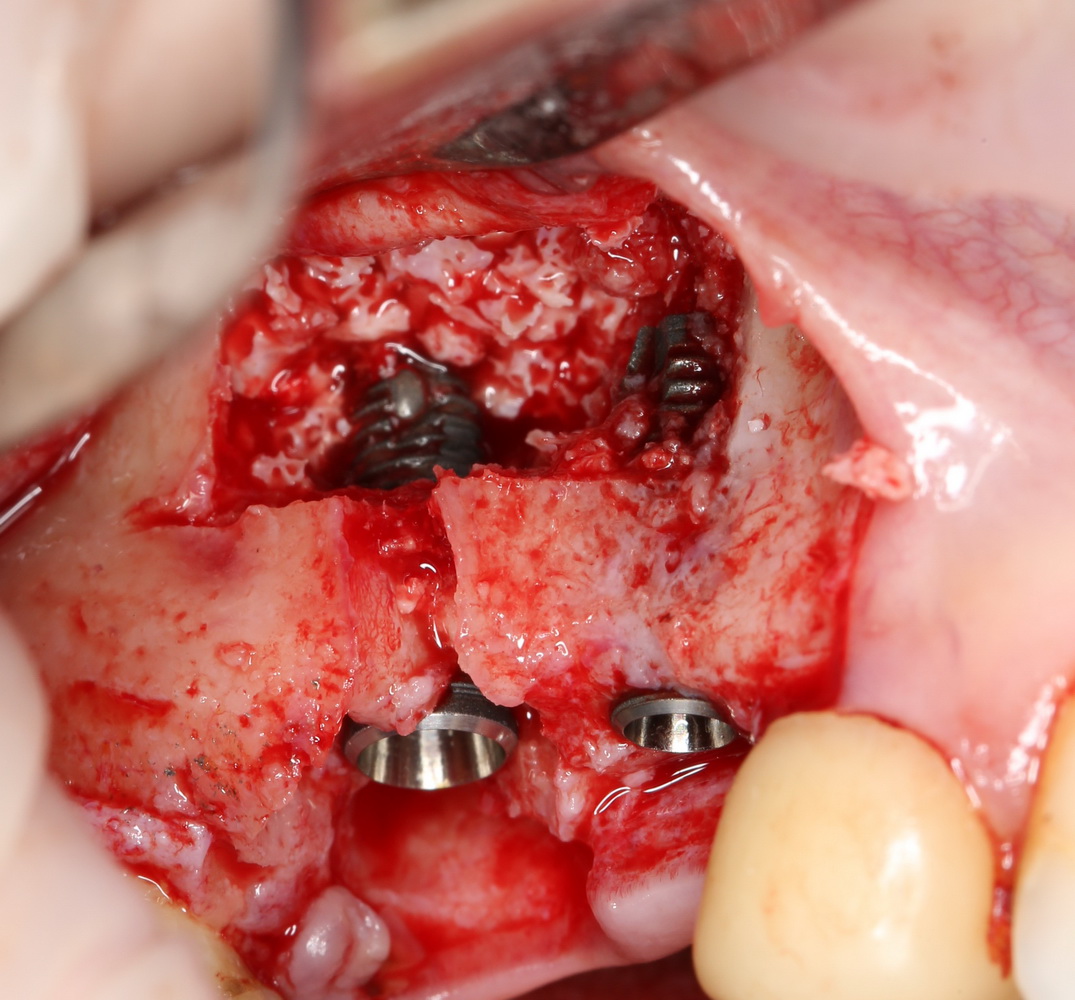

Ничего не стоит поставить имплантат в такие объемы кости и при таком качестве слизистой оболочки:

Обратите внимание: даже там, где отсутствовала вестибулярная стенка лунки, восстановилась костная ткань:

Теперь мы просто ставим имплантат. Без синуслифтинга. И без проблем со стабилизацией:

А качество и объем слизистой оболочки настолько хороши, что можно сразу поставить формирователь десны: